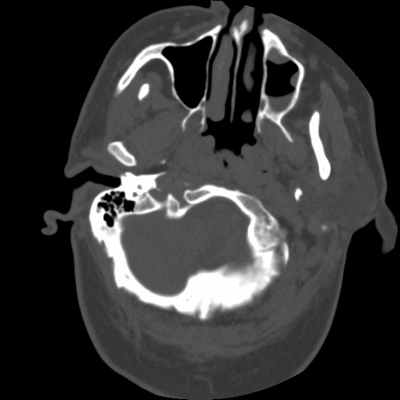

Не стоит забывать и о Ecchordosis physaliphora* (Клин. наблюдение 3). Это врожденная доброкачественная гамартома, которая формируется из нотохордальных зачатков и может встречаться в любой кости, начиная от основания черепа, оканчивая крестцом. Как правило, протекает бессимптомно и является случайной находкой при проведении КТ или МРТ. Выглядит как дефект ската, четко отграниченный и с гладкими контурами, без агрессивного компонента [5]. В литературе описан случай симптомного течения Ecchordosis physaliphora [6], однако, это, скорее, исключение из правил.

Вот такие изменения в пазухах можно найти у каждого больного прошедшего исследование по неврологическим жалобам, и воля ваша, отмечать их или нет (в платных чаще отмечают, в государственных игнорируют)

А вот увидев такую картинку, у такого же неврологического больного, вы не просто должны, вы просто обязаны отразить ее, и даже указать нозологию